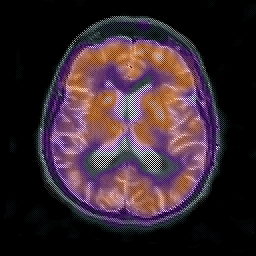

Alzheimer's disease: overlay -- Slice #14

[Home][Help][Clinical] Slice 14